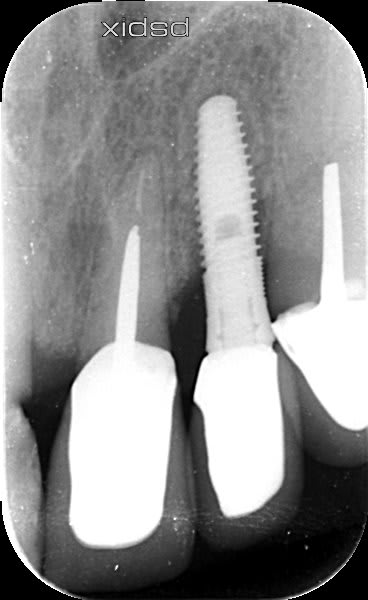

Bonjour, auriez-vous une idée concernant la marque et le modèle de cet implant ?

Possiblement un BIS de chez Biotech

https://www.spotimplant.com/fr/implants-dentaire/biotech-dental/bis-conic